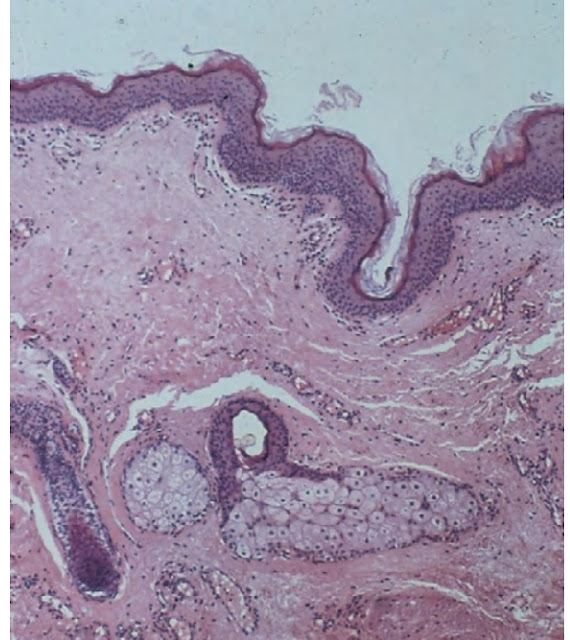

Histopathological features

• The lining is orthokeratinized squamous epithelium.

• Exhibiting a variable number of dermal appendages such as hair follicles sebaceous glands and erector pili muscles.

• Lumen is filled with desquamated keratin sebum and hair shafts.

• There is a sorrounding zone of compressed connective tissue.

• Generally free of inflammation.